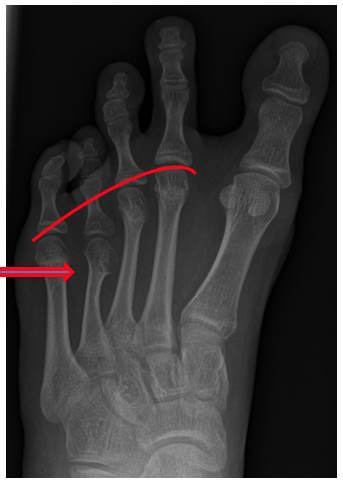

Bei der Brachymetatarsie handelt es sich um eine Blickdiagnose. Die Verkürzung des Mittelfußknochens geht mit einer Verkürzung des gesamten Strahles einher. Dadurch erscheint die betroffene Zehe verkürzt.

Ein Röntgenbild im Stand in dorso-plantarer (d.p.) und streng seitlicher Ausrichtung zeigt die Lokalisation und das Ausmaß der Verkürzung.